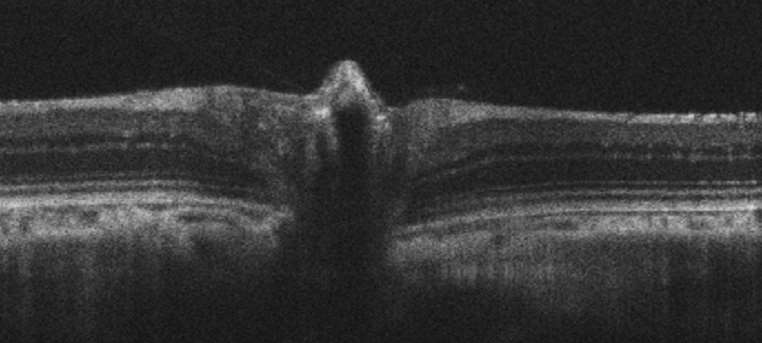

NAVSAM has a wide range of commercial (Bioptigen OCTs, Zeiss slit lamps, Phoenix Micron IV, Phenosys OMR) and custom (multiline cSLO, SD-OCT multifocal ERG) devices capable of image collection and measurements of species spanning zebrafish to swine.

• Proveo 8 surgical microscope with intraoperative EnFocus OCT, purchased through S10OD030229